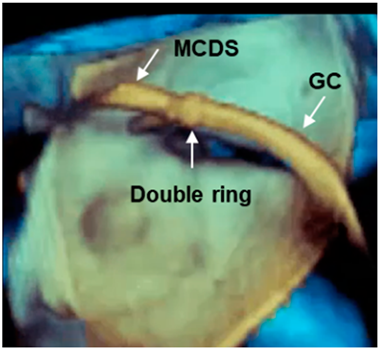

| Long segment of catheter | The pyramidal data set embraces large volumes of the 3D space and allows the visualization of long segments of guide catheter (GC) without moving the probe. Moreover, small details such as the double ring at the tip of the GC can be visualized. MCDS = mitral clip delivery system. |  |